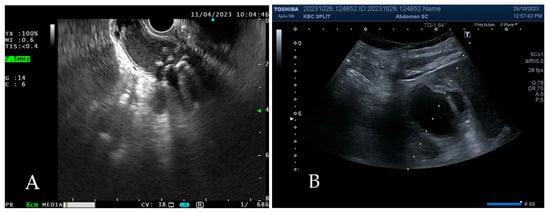

3.1.2. Procedure

3.1.3. Duration